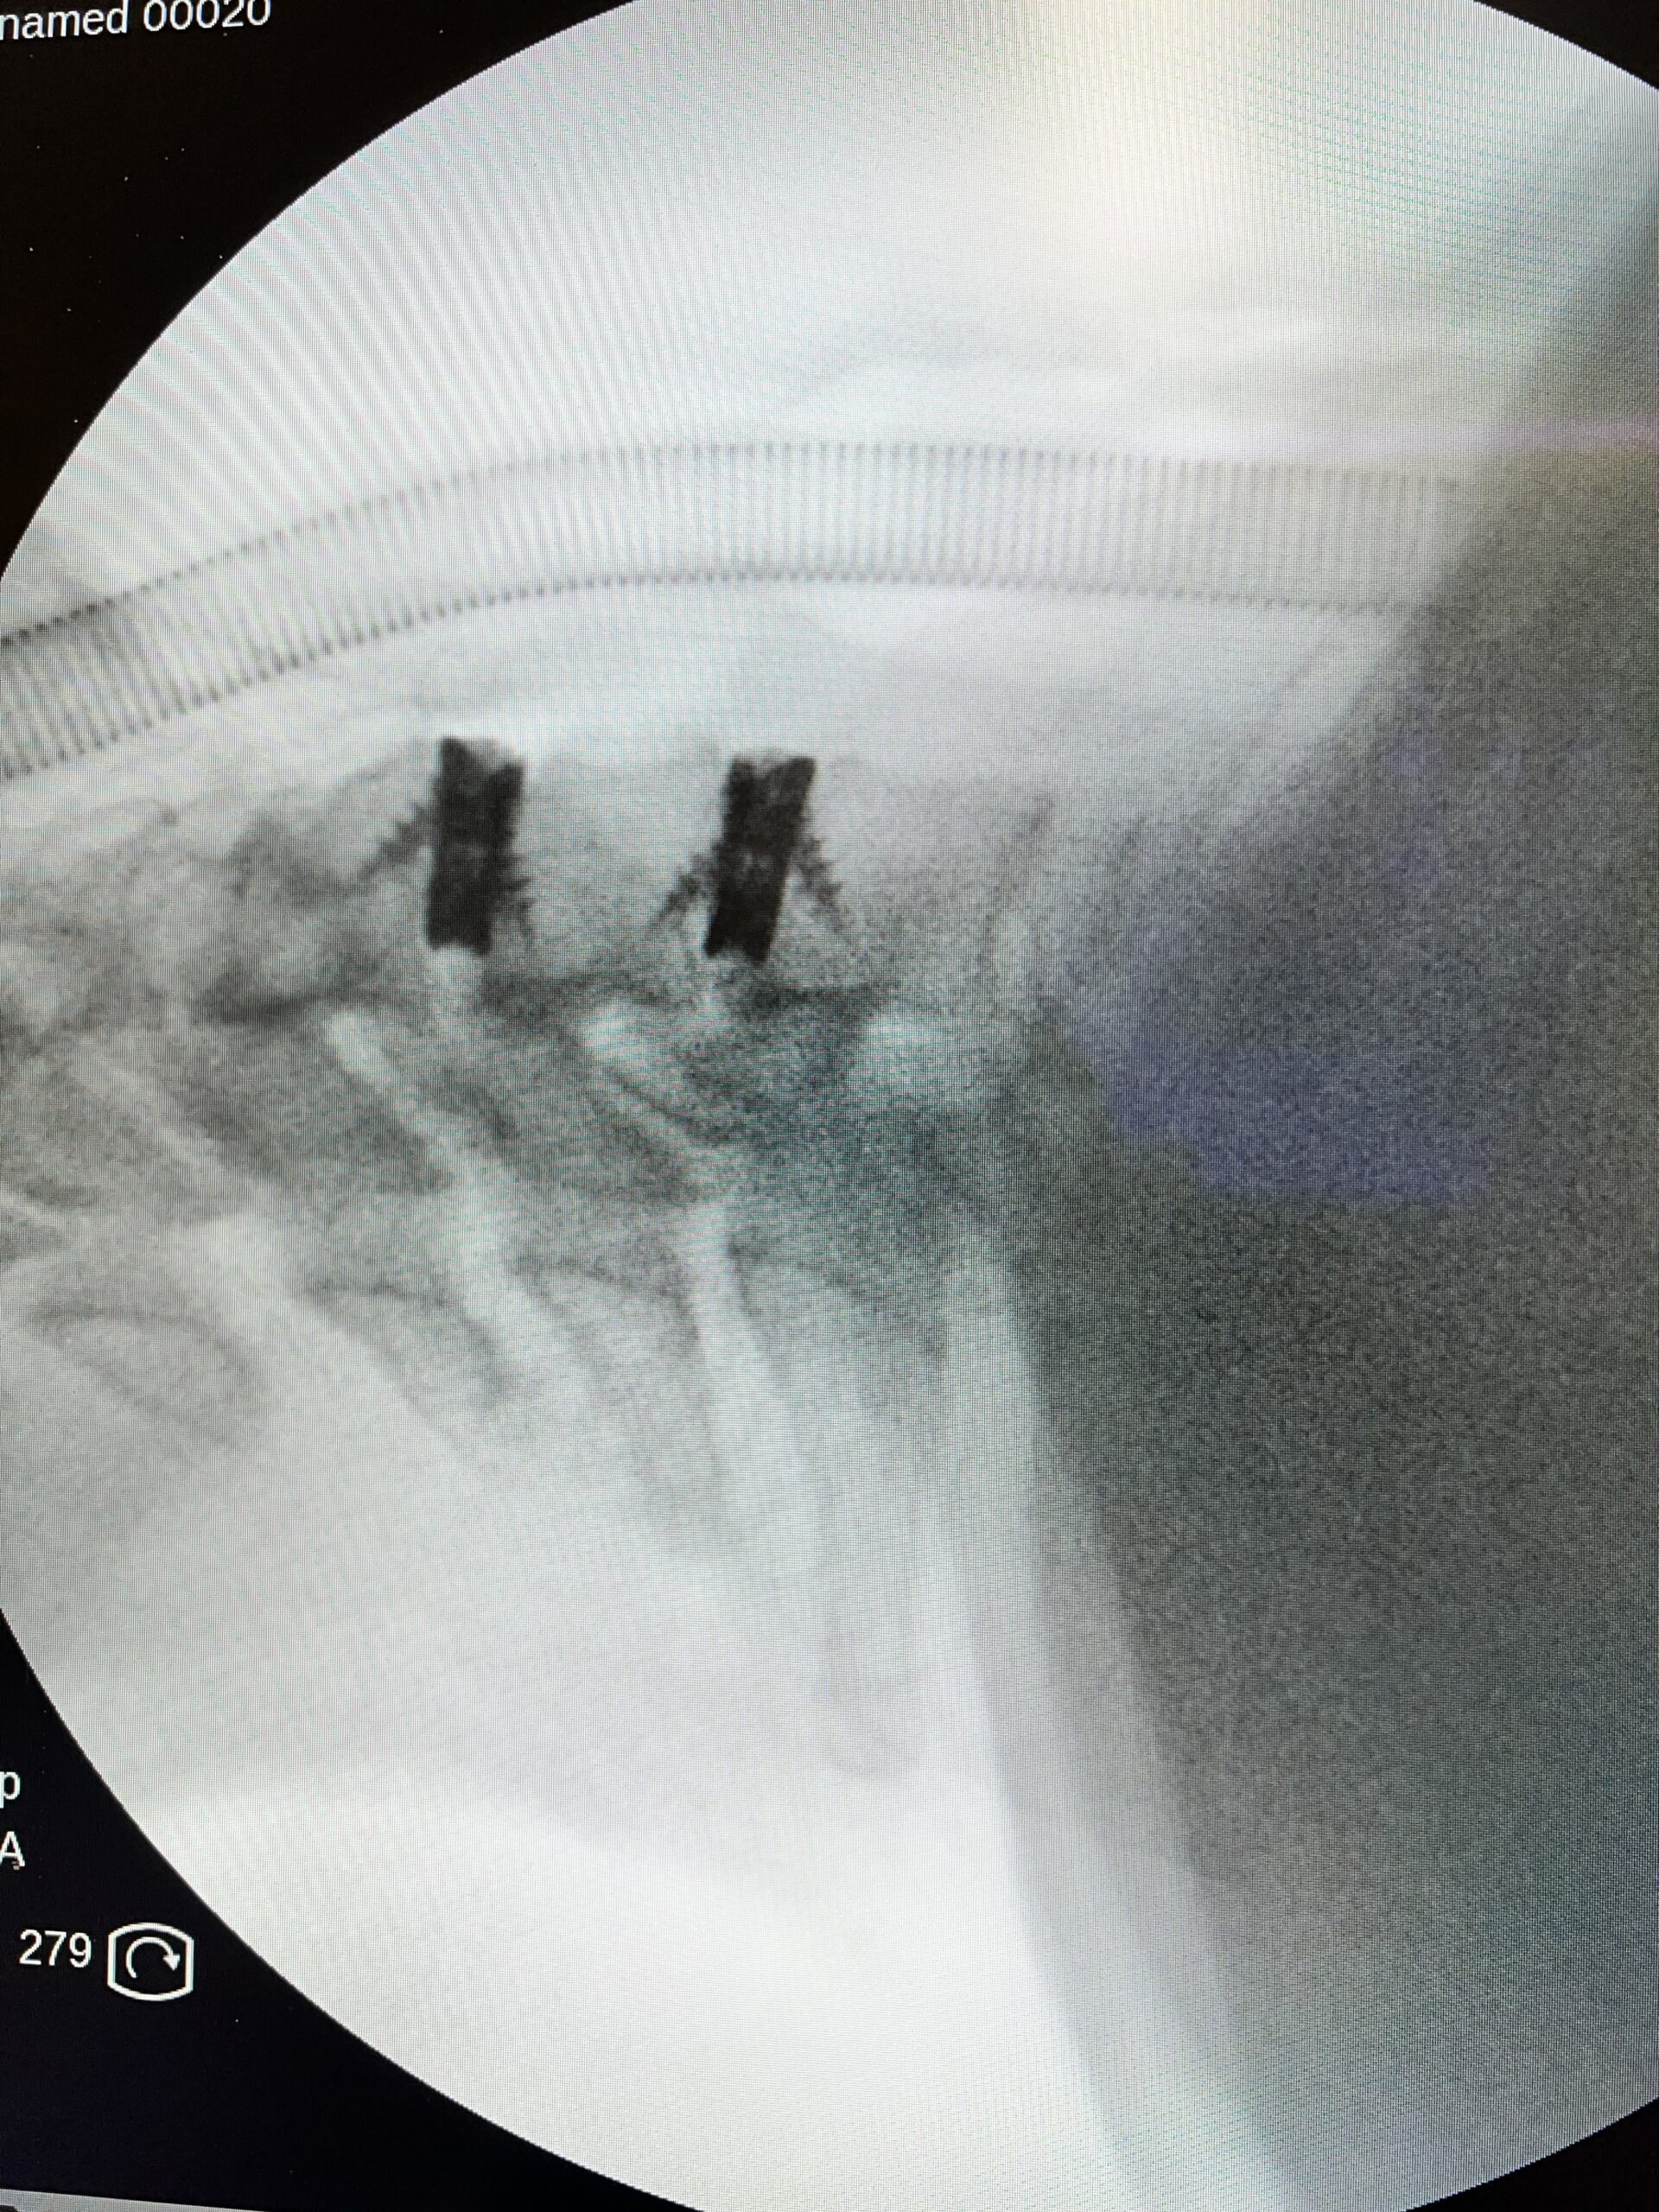

En algunos casos, la cirugía abierta es la única alternativa para mejorar la calidad de vida del paciente. En estas situaciones, estamos especializados en realizar procedimientos bajo los principios de la cirugía mínimamente invasiva, con el objetivo de preservar al máximo los tejidos sanos y la anatomía del paciente. Gracias a los avances en técnicas […]

Como uno de los neurocirujanos en Barcelona con mayor experiencia en técnicas mínimamente invasivas, he tratado a más de 600 pacientes con patologías neuroquirúrgicas mediante cirugía endoscópica. Esta trayectoria me posiciona como un referente en neurocirugía mínimamente invasiva y procedimientos de endoscopia de columna.

Actualmente realizo intervenciones de endoscopia de columna cada semana, lo que me ha permitido perfeccionar la técnica y establecer un flujo de trabajo altamente eficiente. Gracias a nuestros protocolos quirúrgicos, la tasa de complicaciones, incluso en casos leves, es inferior al 1%, lo que garantiza la máxima seguridad y confianza para nuestros pacientes.